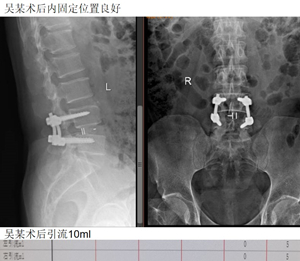

然后是吴某,双下肢疼痛麻木半年。入院肌间隙入路下L4/5肌间隙入路下腰椎融合手术。术后2天拔管,5天出院。

术后引流仅10ml。